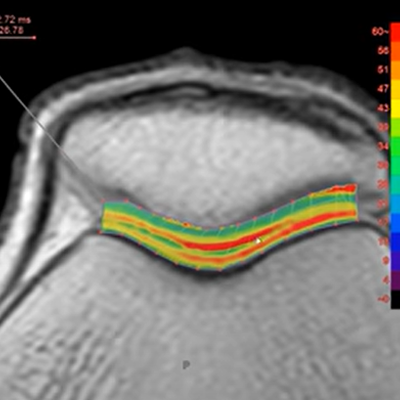

Using MR data with different TE and spin lock times, this protocol measures T2, T2*, or T1rho values of the specified ROI and shows color maps.